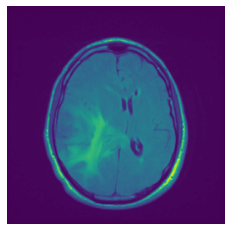

In figure 3, we present qualitative examples of different masking strategies. It is observed that, unlike context prediction and restoration, our method tends to propose targeted masks like the tumor regions or regions with abnormalities and avoids masking less helpful regions. However, it should be noted that Intelligent-Masking does not necessarily mask the tumor regions but considers all areas of interest that results in better feature learning. Examples of other masking samples are provided in supplementary materials. Furthermore, in medical images, unlike natural scenes, the structures are very local with imbalanced information throughout an image. Therefore, random masking strategies as shown in Fig 3 operate ineffectively by masking non-informative regions.

Refer to caption

(a) Original

(b) Intelligent-Masking

(c) Context Prediction

(d) Context Restoration

Figure 2: Qualitative examples of compared method’s strategies for masking